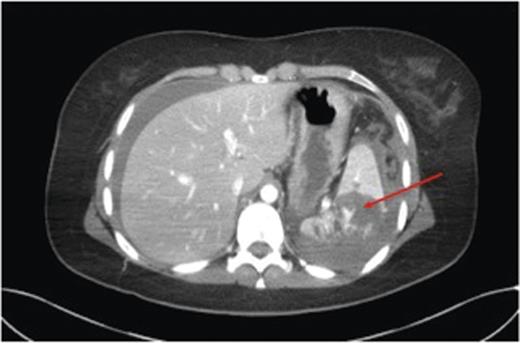

An urgent contrast-enhanced computed tomography (CECT) scan of head, neck, thorax, abdomen and pelvis was performed, demonstrating a Grade 4/5 splenic laceration with several foci of active haemorrhage and a large volume of peri-splenic free fluid consistent with blood with no other intra-abdominal injuries (Fig. 1). Following review, a decision was taken to perform angiography with a view to selective angio-embolization as the patient remained haemodynamically stable. Contrast angiography demonstrated multiple small pseudoaneurysms within the peripheral branches of the splenic artery with active contrast extravasation. The splenic artery was selectively catheterized and embolized at its mid-point with several coils (Fig. 2). At the end of the procedure, collaterals were seen supplying the residual non-injured splenic tissue, with the absence of active contrast extravasation. The patient was transferred to the intensive care unit for continuous haemodynamic monitoring for 36 h. Appropriate additional plain facial and long limb imaging was performed when stable, and no additional injuries were noted. She made an uneventful recovery and was discharged 9 days following admission. An abdominal ultrasound scan, 6 weeks later, confirmed almost complete resolution of the peri-splenic haematoma.

CECT demonstrating a grade 4 splenic injury with contrast extravasation suggesting active haemorrhage (arrow).